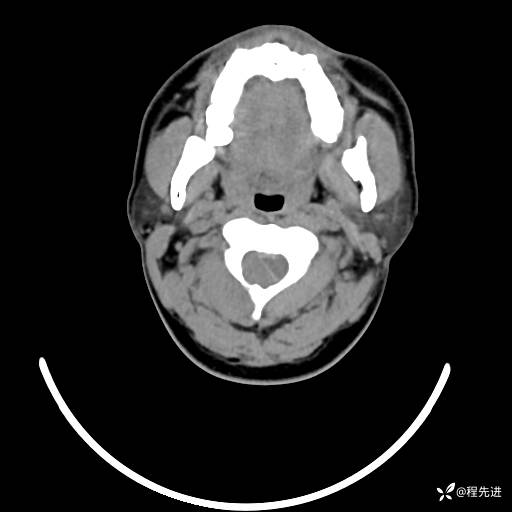

CT平扫+增强: